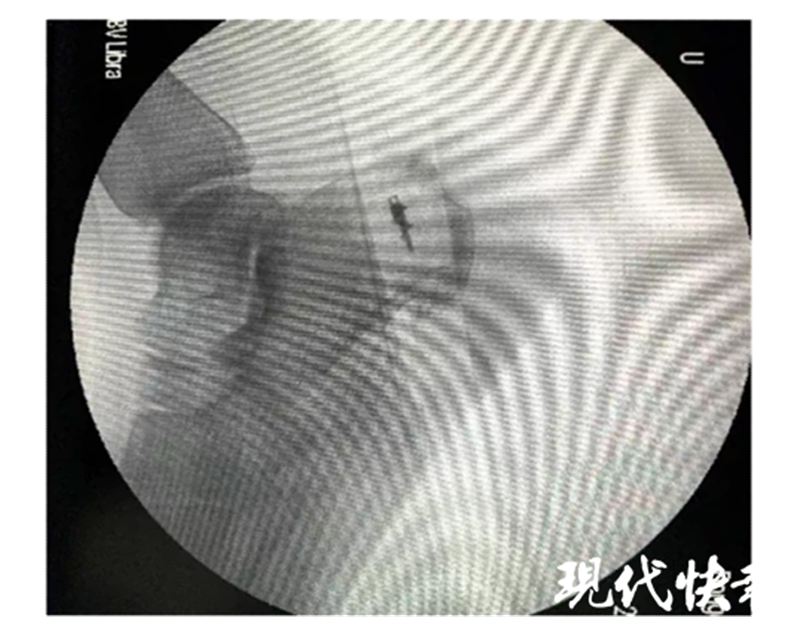

△吴加东团队手术中

结合患者病情,在征得本人同意后,吴加东团队为其实施了“骨赘切除+跟腱固定”手术。团队利用微型摆锯将骨赘彻底清除,并将锚钉埋入跟骨内利用尾线将跟腱重新编织缝合,共用时一个多小时。术后,董女士跟骨后上结节异常骨性凸起清除彻底,症状缓解,目前已康复,行走自如。

△患者术前及术后X-ray片